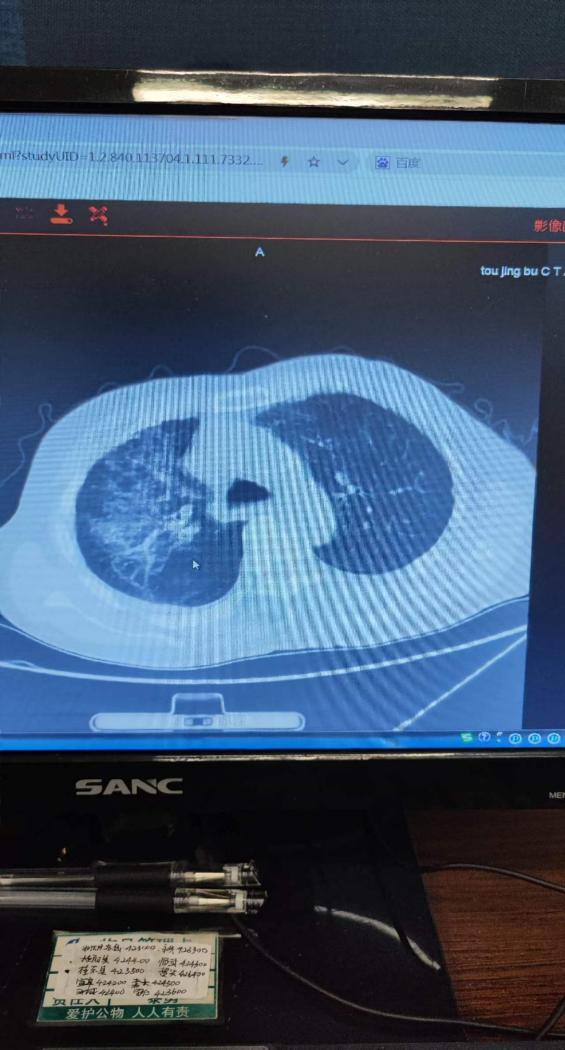

为了明确诊断并制定最佳治疗方案,老年病科医务人员为他进行了全面的检查。结果显示,陈老先生心肌损伤严重,各项炎症反应指标均显著升高,肺部CT检查显示,患者肺部感染情况严重,还具有双侧胸腔积液,各项检查结果无一不在昭示着陈老先生病情的严重性。

在治疗过程中,科室医护人员对陈老先生给予了无微不至的护理和关爱。大家不仅对他的身体状况进行密切监测,还对他的心理状态、营养状态进行了全面的评估和干预。为了缓解他对疾病的恐惧与焦虑,医护人员还为他提供了心理疏导。但就在此时,陈老先生的身体状况出现了进一步的恶化,气促越来越严重,心电监护提示血氧饱和度低于80%,提示着呼吸衰竭,复查肺部CT也提示炎症较前增加。陈运红凭借着丰富的治疗经验,怀疑老人肺部存在着真菌感染,陈运红说,“由于真菌感染在老年人,特别是长期卧床体质虚弱的老年人中较为常见,我们在治疗过程中需高度怀疑陈老先生感染真菌性肺炎的可能。”